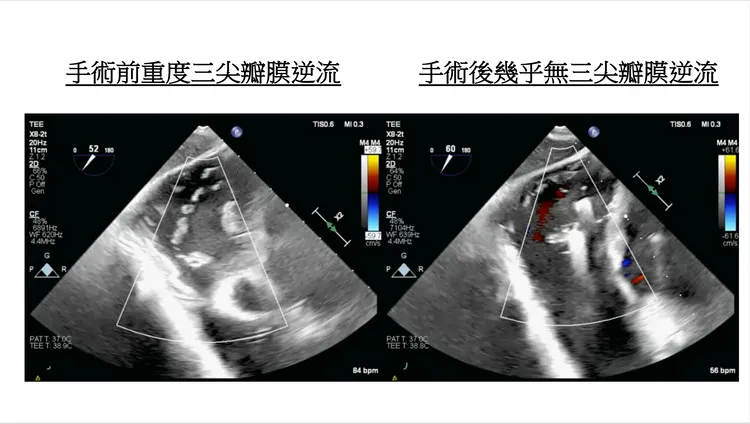

針對三尖瓣膜逆流的病因,許喬博提到,可分為原發性及次發性,僅1成屬三尖瓣膜本身有問題的「原發性」,另高達9成為「次發性」,可能是二間瓣膜問題造成、心律不整等因素,考慮到手術本身風險,三尖瓣逆流的治療一般都達重度逆流才採取手術。

至於北榮本次使用的經導管三尖瓣膜修補技術,是用2個以上的小夾子把瓣膜給「夾起來」修補,不但不需使用體外循環心肺機,傷口也相當小,7成病患在術後1年內可維持中度以下的三尖瓣逆流,大幅改善心衰竭症狀。